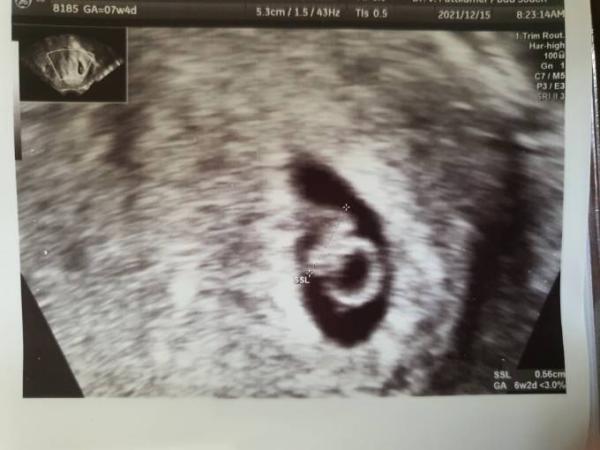

Hi ihr Lieben, ich war heute wieder bei meiner FÄ und durfte das Herzchen schlagen sehen, sie meinte sogar sehr heftig. Allerdings wurde ich wieder zurückdatiert, insgesamt nun um 9 Tage und es ist 6mm groß (als sie geknipst hat waren es 5.6mm, sie sagte aber, es seien 6mm). Einerseits freue ich mich natürlich riesig, andererseits ist nach 12 Jahren Beten und Hoffen die Angst mein ständiger Begleiter. Am 7.12 war es 3.4mm groß und ich wurde auf 6+0 zurückdatiert. Nun also knapp 6mm und 6+2. Wächst das nicht etwas langsam? Mein nächster Termin ist erst am 11.1., also in knapp einem Monat. Das werden zittrige Weihnachten haha